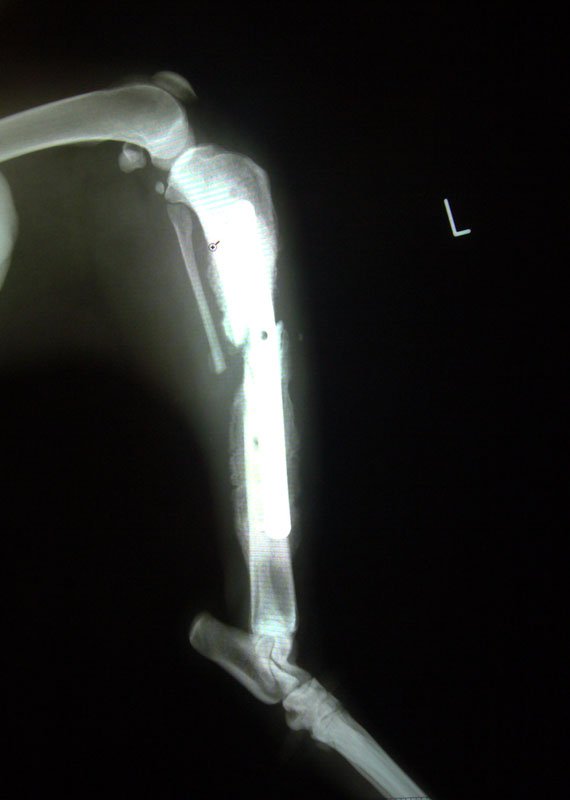

Ο τυχεράκιας ο Lucky (ε, τι να τον έβγαζαν δηλαδή, Βλαδίμηρο;) βρέθηκε χτυπημένος στο διάζωμα της Εθνικής Οδού τον Ιανουάριο. Το σκυλί χειρουργήθηκε σε μπρος και πίσω πόδι, που είχαν κατάγματα, και στη γνάθο. Παραμένει κούκλος, σα να μην είχε σπάσει τίποτα. Το adespoto.gr (ακολουθούν συστάσεις), που βοηθά στην υιοθεσία του, με ενημερώνει ότι γίνεται και εξωτερική οστεοσύνθεση στο πίσω πόδι για να μπορεί το σκυλί σε λίγο να τρέχει στις εξοχές μαζί με όποιον τυχεράκια του προσφέρει ένα σπίτι για να αναρρώσει. Προς το παρόν αυτός ο σκύλαρος παραμένει περιορισμένος σε ένα μικρό κλουβί κτηνιατρείου. Δηλαδή αυτό που θα κάνει όποιος τον πάρει δεν θα είναι απλή υιοθεσία, θα είναι απελευθέρωση.